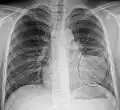

The discovery of x-rays made it possible to determine the anatomic type of pneumonia without direct examination of the lungs at autopsy and led to the development of a radiological classification. Early investigators distinguished between typical lobar pneumonia and atypical (e.g. Chlamydophila) or viral pneumonia using the location, distribution, and appearance of the opacities they saw on chest x-rays. Certain x-ray findings can be used to help predict the course of illness, although it is not possible to clearly determine the microbiologic cause of a pneumonia with x-rays alone.